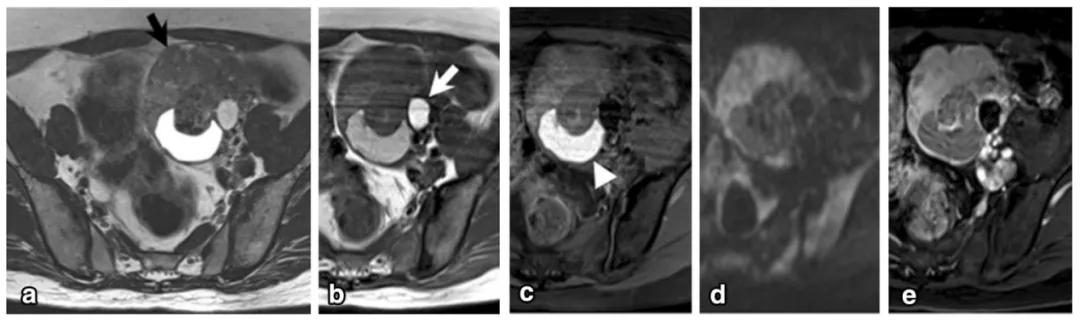

女性,36 岁,睾酮升高,类固醇细胞瘤。T2WI 示右卵巢可见不均匀稍高信号肿物(图 a),增强扫描早期明显强化(图 b)。T1WI 同相位(图 c)及反相位(图 d)可显示肿物内脂质成分,相应 CT 图像呈低密度(图 e)

类固醇细胞瘤是一种罕见的性索间质肿瘤,根据策划细胞来源分为三个亚型:间质黄体瘤、间质细胞瘤及非特异性类固醇细胞瘤,后者最多见。发病年龄跨度大,平均发病年龄约 47 岁。肿瘤可分泌类固醇激素,根据分泌激素不同,临床表现可分为高雄激素和高雌激素两型,高雄激素型最为常见,表现为男性化。肿物可呈实性或多房囊性,大多含有脂质成分曾被称为脂质细胞瘤,多数肿瘤位于卵巢内,周围可有正常卵巢策划包绕,绝大多数为单侧。